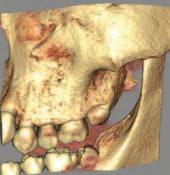

1. What condition is affecting the first permanent molar in Figure 1?

2. What is the estimated global prevalence of the condition according to the European Academy of Paediatric Dentistry (EAPD) Best Clinical Practice Guidelines?

3. List the main aetiological factors that have been linked to this condition.

4. What signs and symptoms of the condition influence clinical management of affected teeth?

Answers on page 45

FIGURE 1: What condition is affecting this first permanent molar?